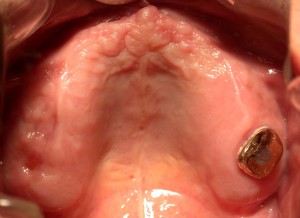

上顎。この上に義歯がのっかていた。

上顎。この上に義歯がのっかていた。